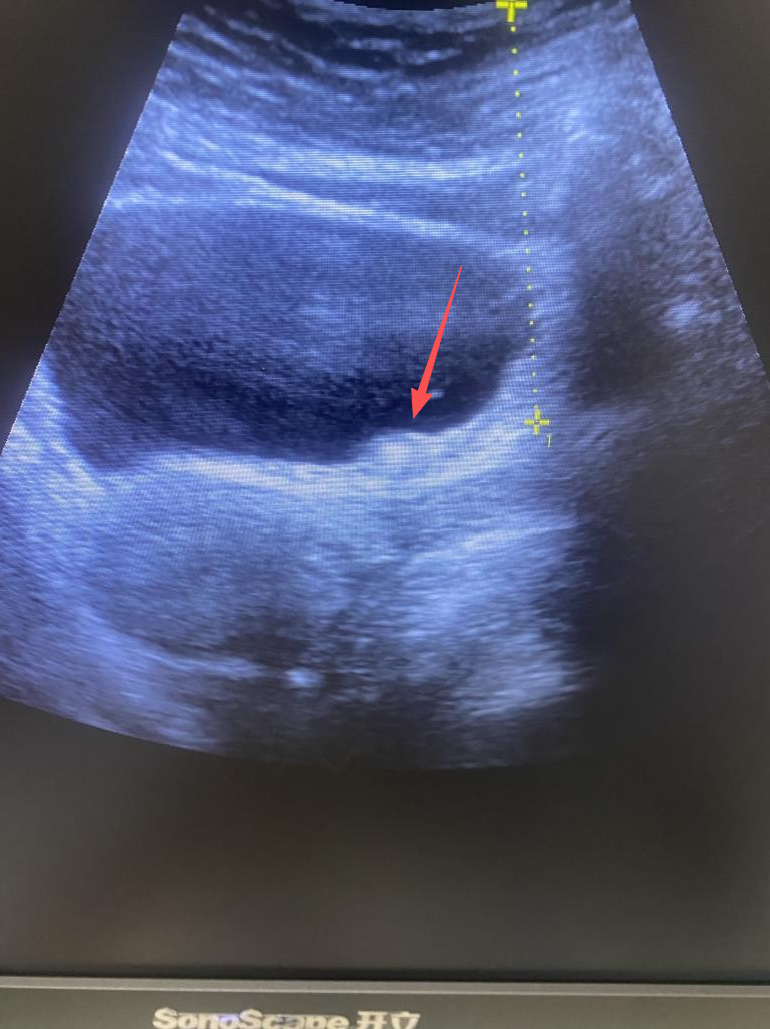

医师使用B超定位系统

给患者实施治疗

并在治疗床旁时刻监测碎石效果

图为输尿管末端结石

可见碎石中结石体积明显缩小